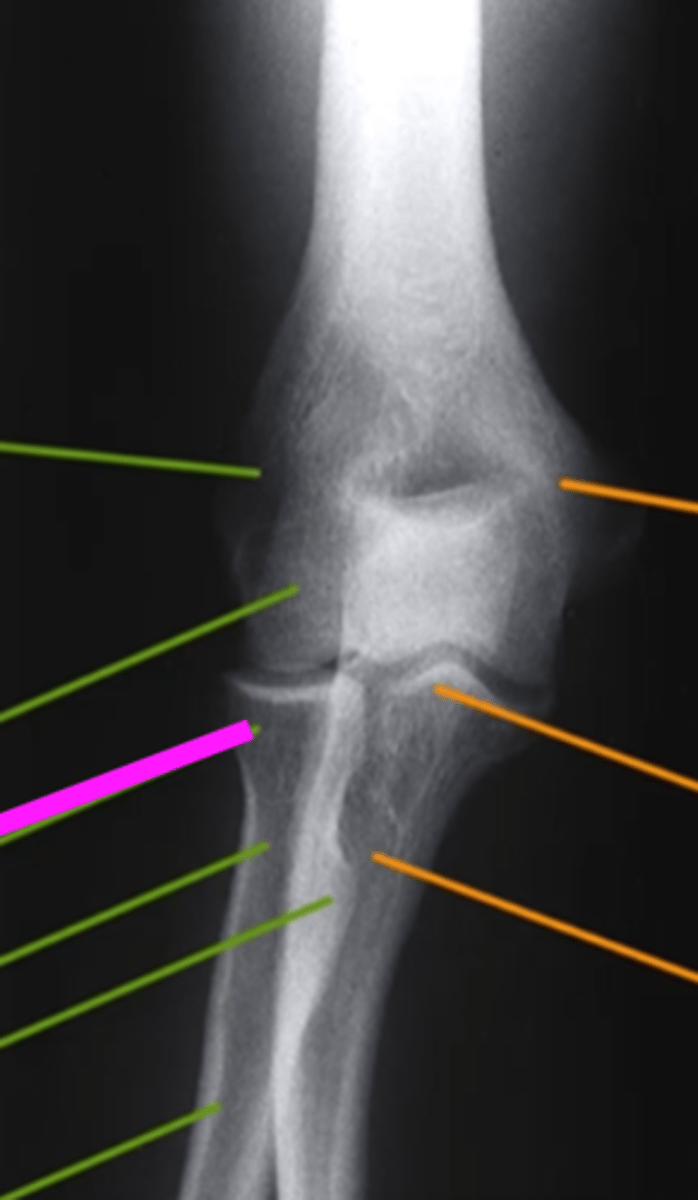

AP Elbow

what view is this

lateral epicondyle

what does the pink line point to?

medial epicondyle

Capitulum

coronoid process

shaft of ulna

shaft of the radius

radial tuberosity

radial head

radial neck